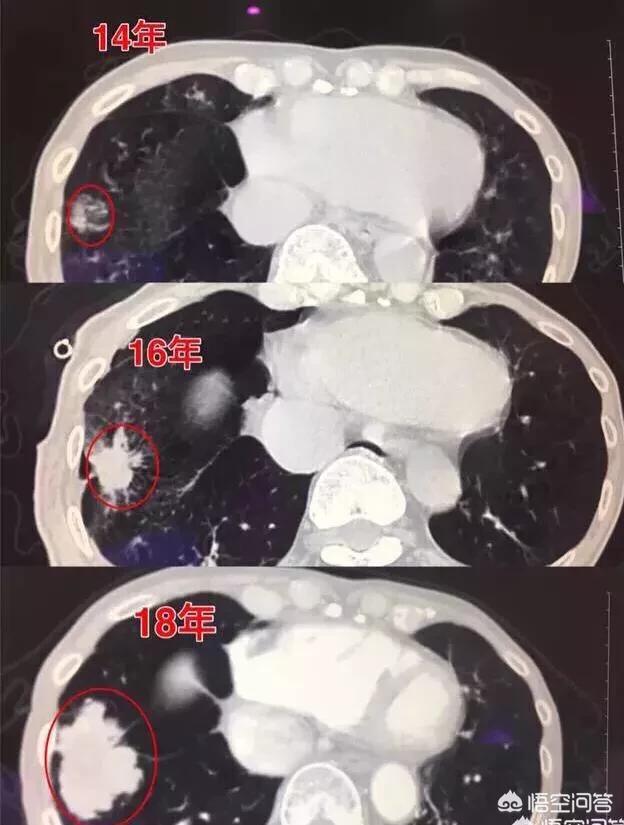

Wachstumsgeschichte eines kleinen Lungenknotens, der sich zu Lungenkrebs entwickelt hat

Gerade vor zwei Tagen, las ich einen Fall, der Patient männlich 57 Jahre alt 3 Jahre der Überprüfung, nur den Prozess der ein Knoten von 0,5 cm groß in Lungenkrebs, jede Überprüfung, der Knoten ist in der Größe zunimmt, aber der Patient nur nicht wählen, Chirurgie.

Bei diesem Beispiel, das 4 Jahre lang beobachtet wurde, wuchs der Klumpen immer weiter.